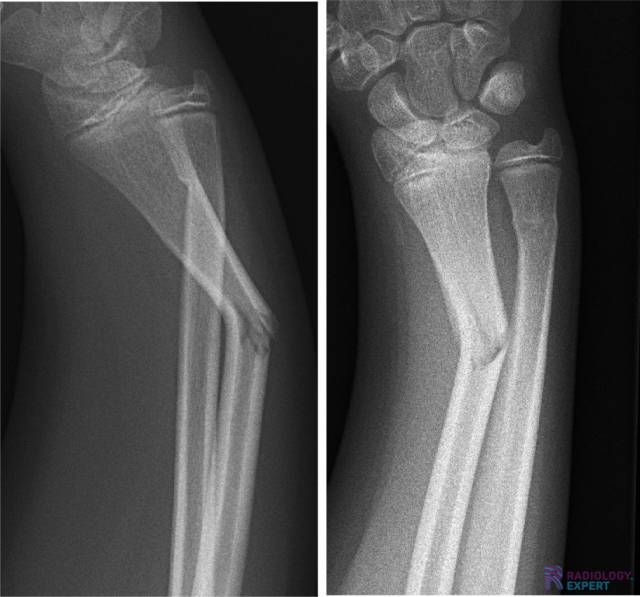

Figuur 1. Laterale en anterior-posterior opname van de linker onderarm/pols. Een kind (9 jaar oud) met distale radiusschacht & ulnaschacht fractuur. Beide tonen een dorso-ulnaire dislocatie over circa een schachtbreedte.